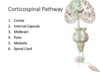

Corticospinal Pathway

__ is where the cell bodies of the UMN of the corticospinal paths originate. From these cell bodies, axons descend into the cortex, where they converge to form the _- __, and pass through the __ __ of the internal capsule inferiorly.

the UMN then moves towards the __ __/crus cerebri, doesn into the __, and then to the ___ __, where the UMN __.

The UMN continues to move down to the __ __, and it SYNAPSES with the LMN in the __ __

PMC is where the cell bodies of the UMN of the corticospinal paths originate. From these cell bodies, axons descend into the cortex, where they converge to form the corona radiata, and pass through the posterior limb of the internal capsule inferiorly.

the UMN then moves towards the cerebral peduncles/crus cerebri, doesn into the pons, and then to the mmedullary pyramids, where the UMN DECUSSATES.

The UMN continues to move down to the spinal cord, and it SYNAPSES with the LMN in the ANTERIOR HORN